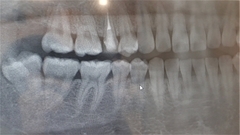

Before(下親知らずの抜歯前) 横に生えた状態で埋まっている親知らず 虫歯がある親知らず 抜歯前の骨の状態のレントゲン像

After(下親知らずの抜歯後) 横に生えた状態で埋まっている親知らずの抜歯後 虫歯がある親知らずの抜歯後 抜歯後の骨の状態のレントゲン像

原因をより詳しく調べるためレントゲンを撮影したところ、右下の親知らずは骨の中に埋まった状態のまま真横に生えて隣接する歯を押しており、接触している奥歯の骨が溶けてしまっています。 そのため、右下の親知らずと隣の奥歯の間には、歯と歯ぐきの境目の溝である「歯周ポケット」が通常よりもかなり深くなっていました。

以上の点から、痛みの原因は深くなった歯周ポケットの中で歯垢が溜まって細菌が繁殖し、親知らず周囲の歯ぐきに炎症が起きる「智歯周囲炎」であると診断しました。

まず、親知らずと骨の中にある神経の位置、歯や周囲の骨の詳細な情報を確認するために、歯科用パノラマデジタル写真で口腔内を撮影します。撮影結果を踏まえ、抜歯方法や施術の難易度をしっかり確認しました。